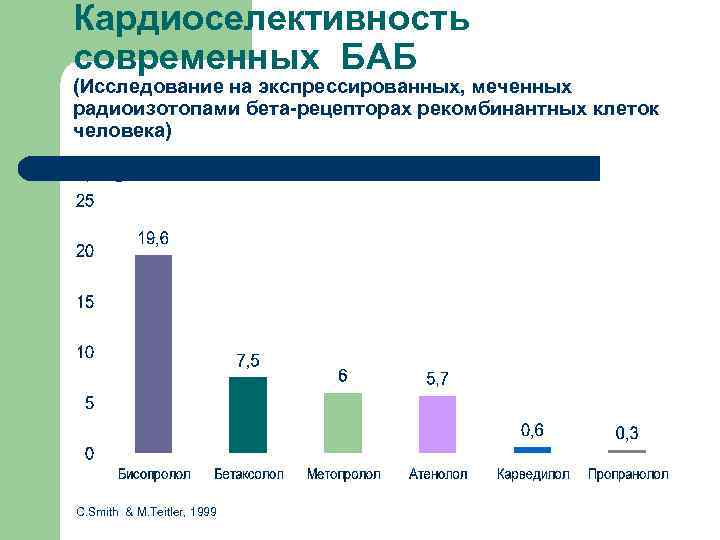

Кардиоселективность современных БАБ (Исследование на экспрессированных, меченных радиоизотопами бета-рецепторах рекомбинантных клеток человека) 1 : 2 C. Smith & M. Teitler, 1999